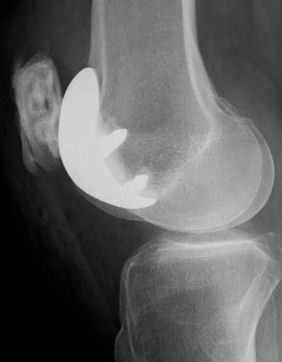

Side view Patello-femoral resurfacing, leaving the rest of the knee alone.